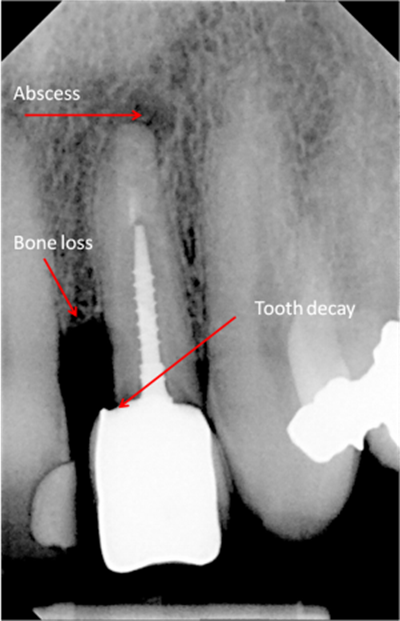

• Bone loss

• Decay between teeth

bone loss